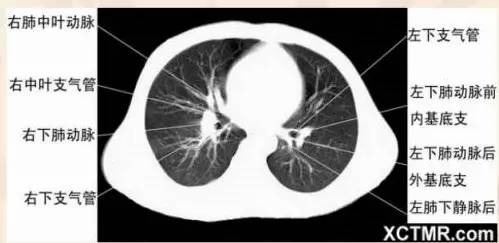

右中叶支气管层面